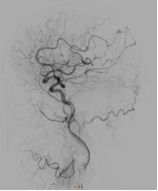

经过周密计划及充分准备,神经外科团队在复合手术室为患者行脑动静脉畸形栓塞术,术中造影提示:大脑前中后动脉、颈外动脉多重供血,引流静脉粗大并形成深部静脉瘤,按照史氏脑血管畸形分级为4级,也就是最高级别的脑血管畸形。造影后,先行栓塞畸形血管团的主要供应血管:右侧大脑后动脉,因血流量大先在血管畸形内填塞三枚弹簧圈,再通过微导管注入液体栓塞剂,成功将畸形血管团大部栓塞。

△介入栓塞后,行右侧颈总动脉造影提示畸形团明显缩小,供血动脉减少